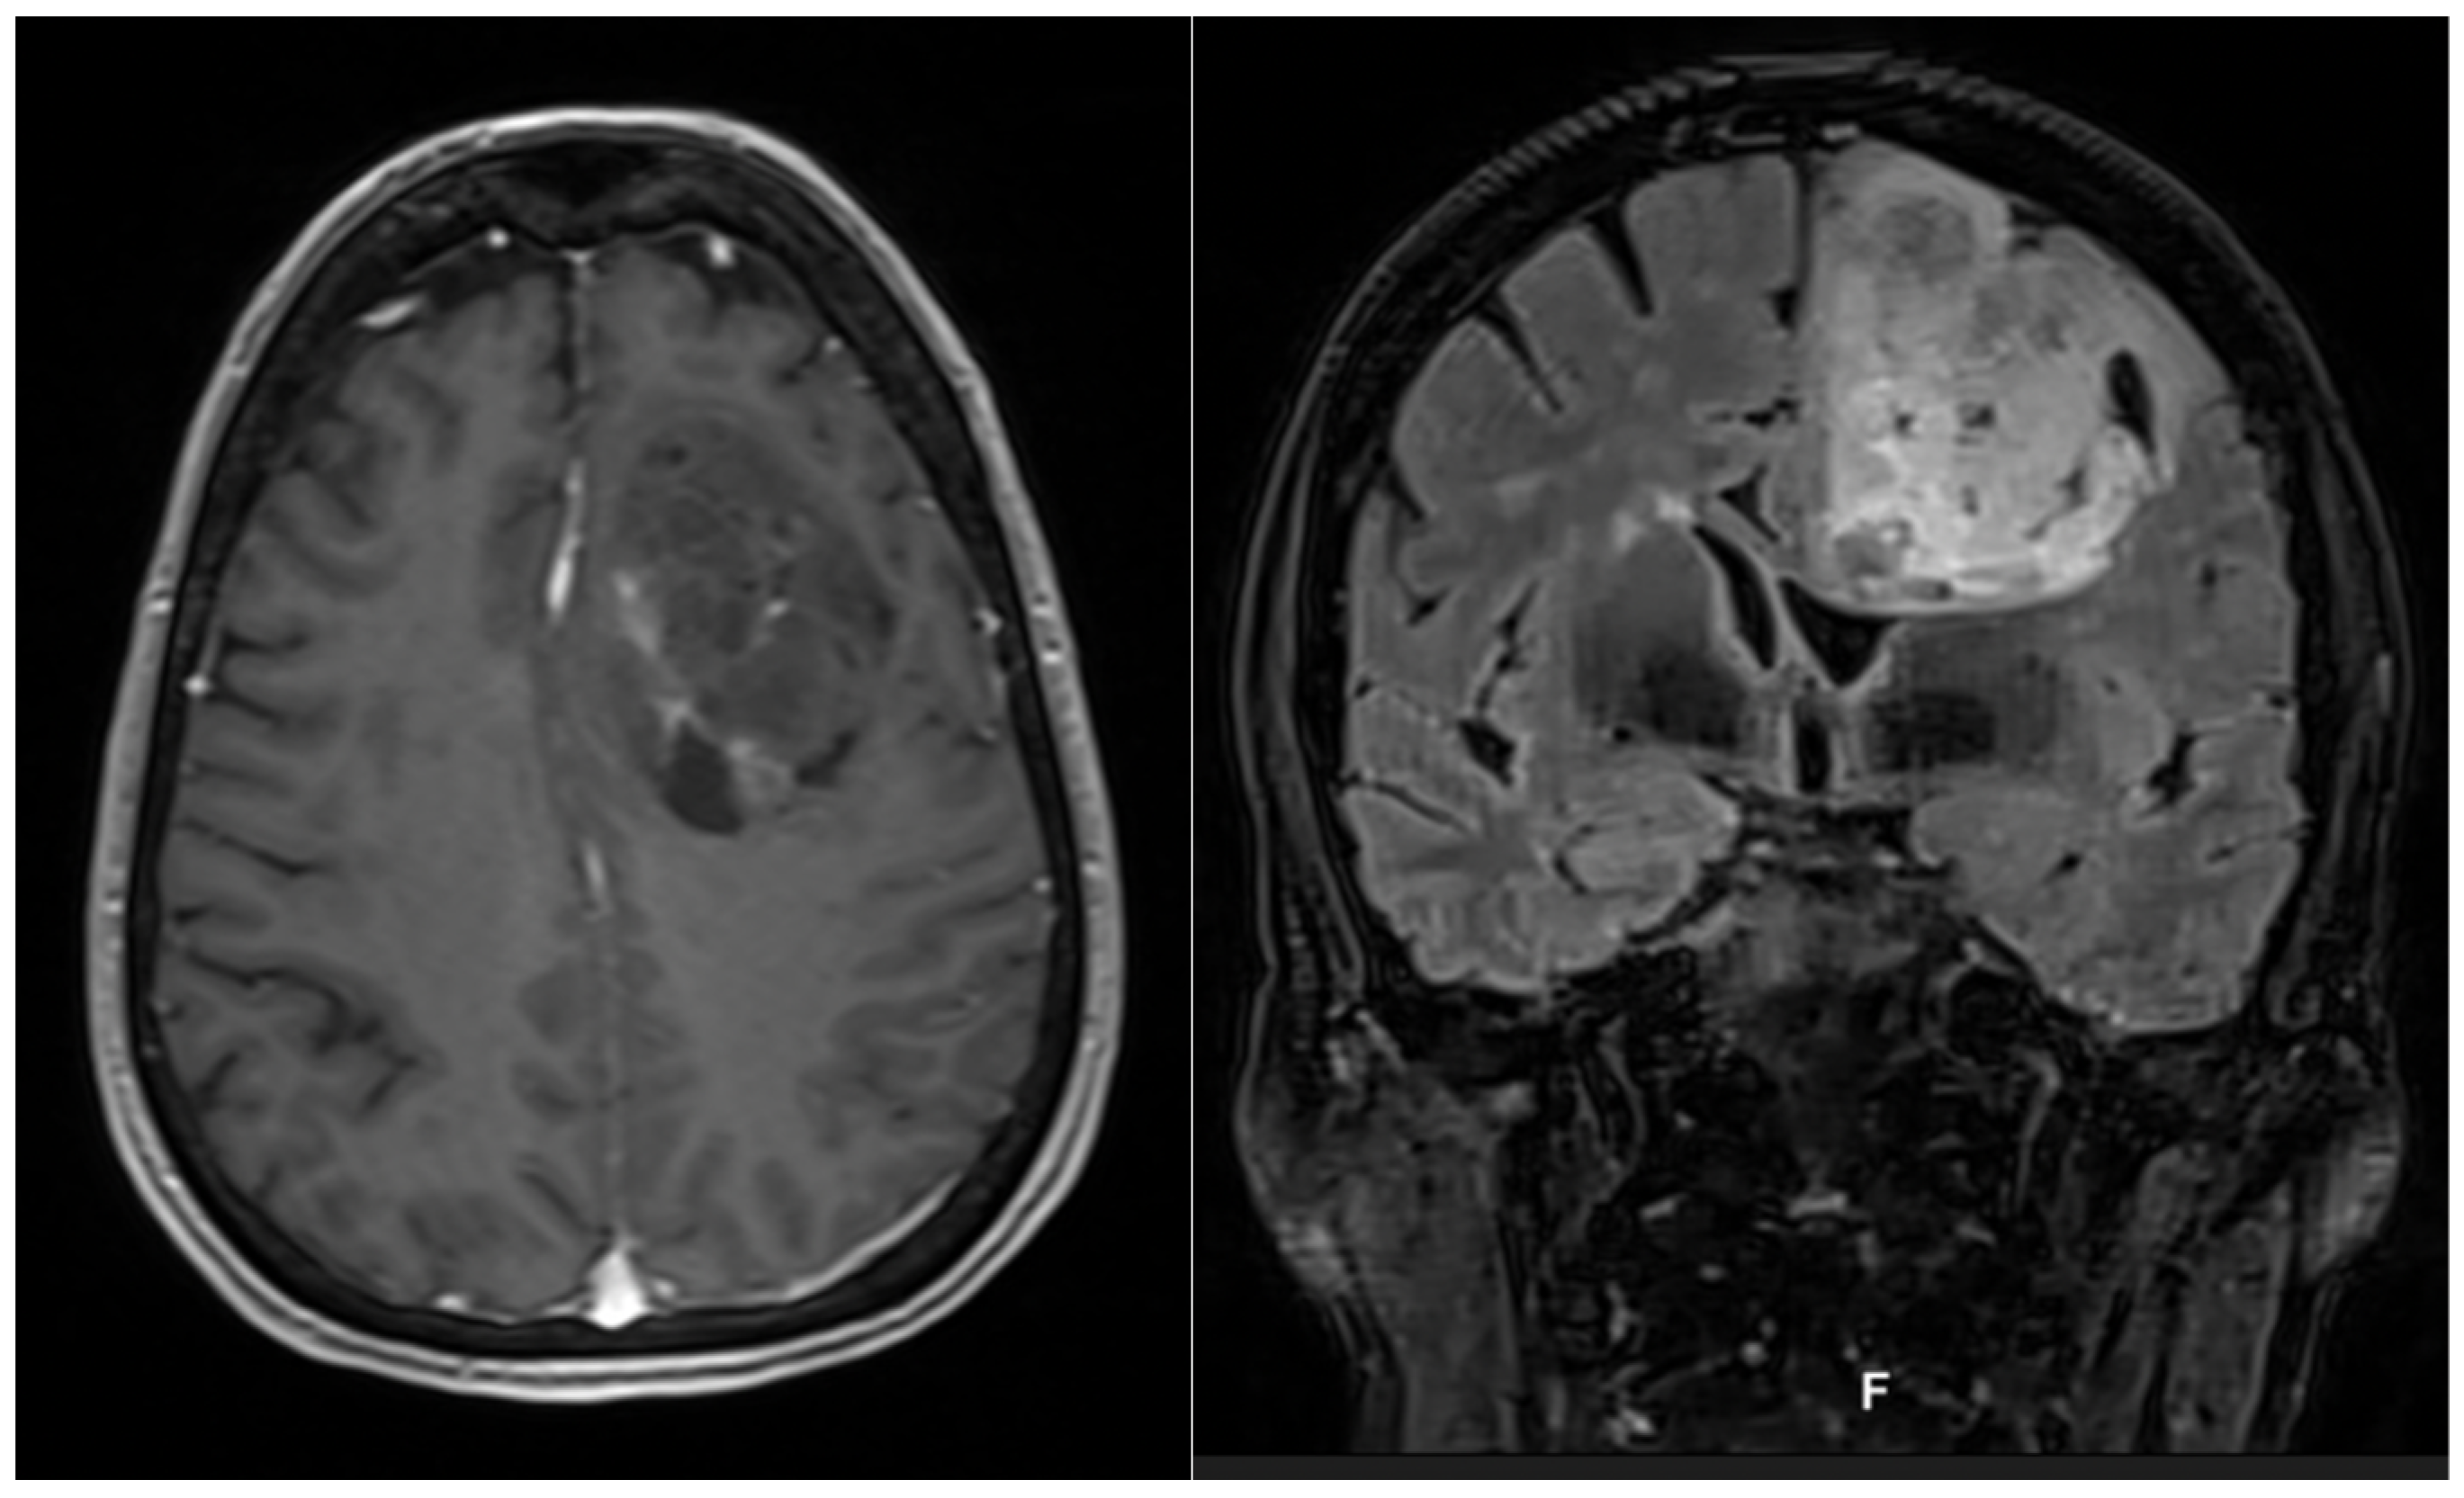

3.1.1. Case 1

3.1.2. Case 2